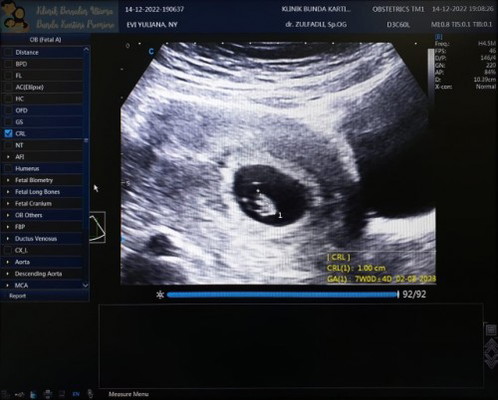

USG ke 2 usianya lebih kecil 2mgg

Alhamdulillah rasanya plong banget, kmrn USG di dokter sblmnya blgnya telat pembuahan, salah hitung, atau BO, langsung drop dwon pikiran kacau. Pas USG lagi MasyaAllah udh ada djjnya 🥺🥺 Semoga sehat smpe lahiran, Kalo sesuai hpht 9mgg 1hari, tapi kalo ukuran janin 7mgg

iya bun, aku kmrn pertama kali USG pas usia 6mgg6hari trnyta baru kantongnya tapi usianya lebih kecil kantongnya ukuran 4mgg, tapi disuruh kembali lagi 2mgg, USG ke 2nya hari ini, bisa jadi pembuahan nya yg gak sesuai mknya lebih kecil 2mgg , gpp bun smngat,